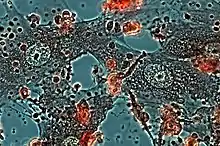

Structurally, epithelioid cells (when examined by light microscopy after stained with hematoxylin and eosin), are elongated, with finely granular, pale eosinophilic (pink) cytoplasm, and central, ovoid nuclei (oval or elongate), which are less dense than that of a lymphocyte.[4] They have indistinct shape and often appear to merge into one another, forming aggregates known as giant cells. When examined by transmission electron microscopy in epithelioid cells in the field of Golgi lamellar complex are taped not only zonated, but also sleek vesicles with dense center, and also great many (more than 100) large granulas with diameters up to 340 nm and with finegranular matrix more light than in macrophage granulas, sometimes with perigranular halo. “The most prominent feature of these cells is the enormous Golgi area; up to 6 individual stacks of Golgi cisternae may be present as well as a few bristle-coated and numerous smooth vesicles”.[5][4] Epithelioid cells have tightly interdigitated cell membranes in zipper-like arrays that link adjacent cells.[3] This cells are central in the formation of granulomas, which are associated with many serious diseases.[4] In granulomas, epithelioid cells perform the functions of delimiting.[3]

It is shown that the epithelioid cell cytoskeleton formed by filaments differs significantly from the macrophage cytoskeleton.[6][7] A large increase in the number of filaments occurs in these cells, where filaments (90 to 100 A) surround the cytocentrum as a distinctive annular bundle often branching into the cytoplasm. Due to such cytoskeleton contiguous epithelioid cells display elaborate cytoplasmic interdigitation.[6] By using the quick=freeze and freeze-substitution methods (prompt freezing, penetrating etching and freeze-substitution) it has been shown that the organizations three-dimensional metastructure cytoskeleton of the epithelioid cells, formed in the focus of granulomatous inflammation, more compatible to cytoskeleton characteristic of typical epithelial cell than to cytoskeleton of active and movable macrophages. It is exhibited that the dense webs of intermediate filaments, bound with cores, mitochondrions and other organelles, are supervised everywhere in cytoplasm of epithelioid cells. Some fascicles of actinic filaments were posed in filopodiums below than membranes of the cells. Exact interdigital tripling of membranes of cells between interfacing epithelioid cells were clearly demonstrated. Interdigital filopodiums were identified. The characteristic indication of epithelioid cells is their aggregation with formation tight interdigital triplings as a fastener "lightning", which, apparently, can have the important for the formation of a dense zone of delimitation of the body from the pathogen during the formation of epithelioid cell granulomas.[7]